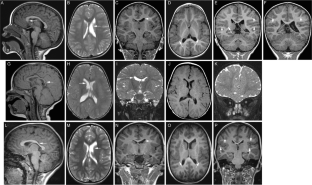

Variants in multiple tubulin genes have been implicated in neurodevelopmental disorders, including malformations of cortical development (MCD) and congenital fibrosis of the extraocular muscles (CFEOM). Distinct missense variants in the beta-tubulin encoding genes TUBB3 and TUBB2B cause MCD, CFEOM, or both, suggesting substitution-specific mechanisms. Variants in the alpha tubulin-encoding gene TUBA1A have been associated with MCD, but not with CFEOM. Using exome sequencing (ES) and genome sequencing (GS), we identified 3 unrelated probands with CFEOM who harbored novel heterozygous TUBA1A missense variants c.1216C>G, p.(His406Asp); c.467G>A, p.(Arg156His); and c.1193T>G, p.(Met398Arg). MRI revealed small oculomotor-innervated muscles and asymmetrical caudate heads and lateral ventricles with or without corpus callosal thinning. Two of the three probands had MCD. Mutated amino acid residues localize either to the longitudinal interface at which α and β tubulins heterodimerize (Met398, His406) or to the lateral interface at which tubulin protofilaments interact (Arg156), and His406 interacts with the motor domain of kinesin-1. This series of individuals supports TUBA1A variants as a cause of CFEOM and expands our knowledge of tubulinopathies.